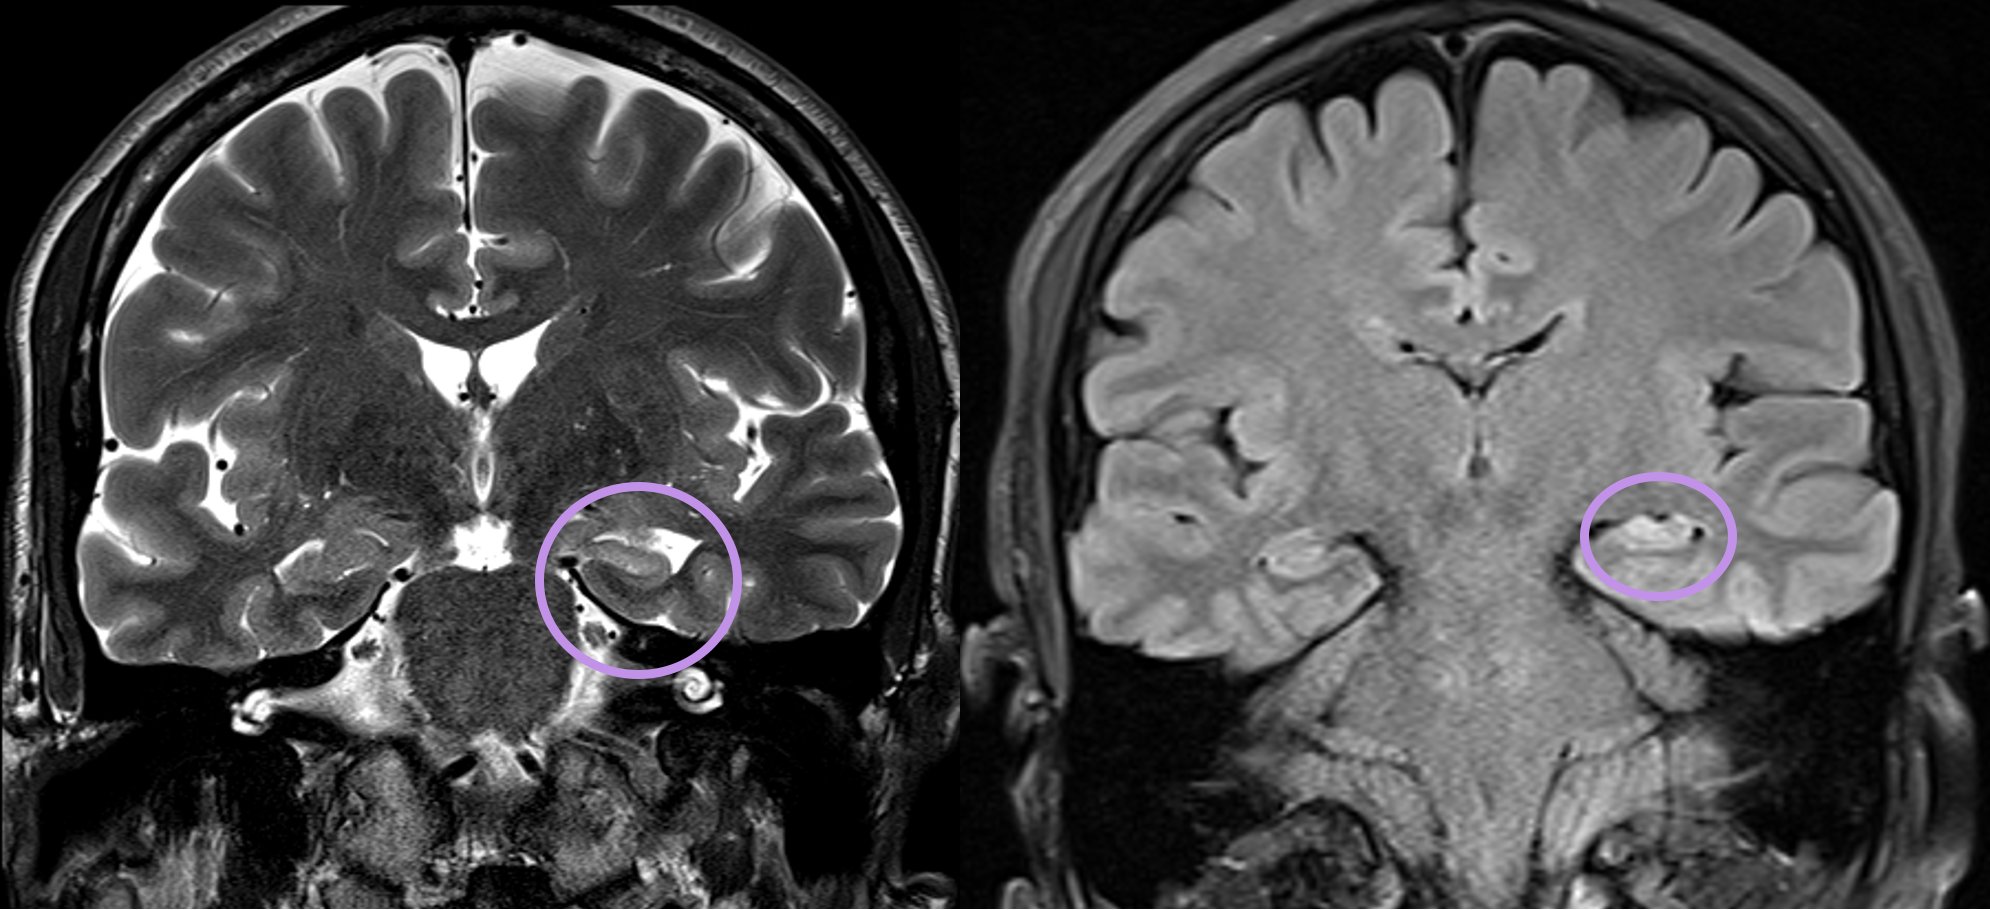

Aaron Rutman, MD On Twitter: "7/8..Note The Hippocampus Is Somewhat

Aaron Rutman, MD on Twitter: "7/8..Note the hippocampus is somewhat twitter.com